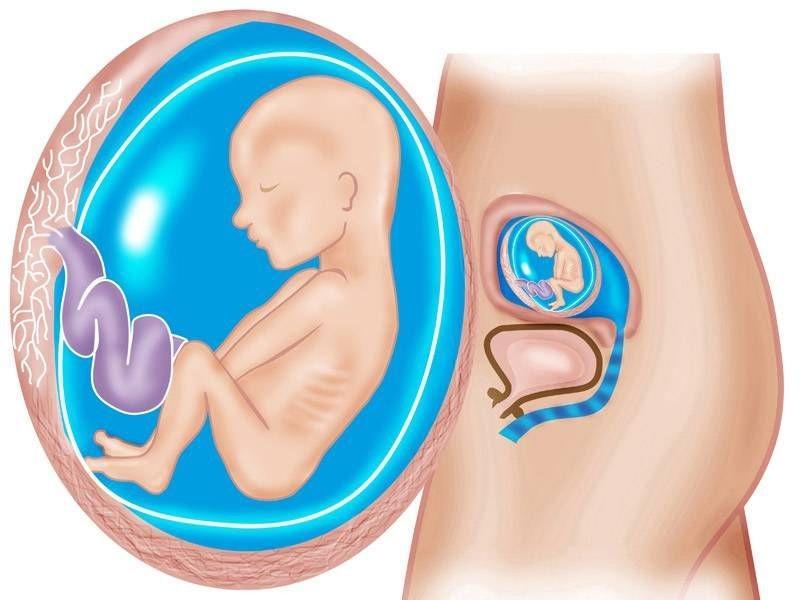

Anne karnında ay ay bebek gelişmi. Normal kiloda bir kadın hamilelik boyunca toplam 12.5 ila 17.5 arası kilo almalıdır. Hafta itibarı ile artık bebeğinizin görüntülerini, kese boyunu ultrasonla görebilirsiniz. Hafta” gibi söylemler duymanızın nedeni budur. Haftasında fetüsün boyu baştan kalçaya yaklaşık 11,6 cm ölçülür ve ortalama ağırlık. 6 aylık gebelik görüntülerinde vücudu orantılı görünür.

7 haftalık gebelik (hamilelik) görüntüsü, gebelikte 7. Hamilelikte 20.hafta 40 haftalık maceranın yarısına gelindiği süredir.20 haftalık gebelik tamamlandığında anne karnında bebeğin boyu yaklaşık olarak 25.cm, ağırlığı ise 300 gram kadardır. Onunla bol bol konuşursanız, doğumdan sonra sesinizi tanıma olasılığı çok yüksek. 6 haftalık büyümeden sonra artık bir greyfurt büyüklüğünde. Anne karnında ay ay bebek gelişmi. Hamilelikte 1 aylık kız bebek ultrason görüntüsü.

19 haftalık ultrason görüntüleri ve 19.hafta bebek gelişimi ile ilgili görüntüler bu dönemdeki değişiklikleri size görsel olarak da anlatacaktır. Hamilelikten önce rahmin, yumruğun büyüklüğündeydi. Hamilelikte 20.hafta 40 haftalık maceranın yarısına gelindiği süredir.20 haftalık gebelik tamamlandığında anne karnında bebeğin boyu yaklaşık olarak 25.cm, ağırlığı ise 300 gram kadardır. Çünkü ilk defa bebeklerini ebeveynlern görmek için sabırsızlaşır. İşte bu nedenden dolayıdır ki, 4 haftadan önce bir hamilelik söz konusu değildir ve yine bu nedene bağlı olarak da 4 hafta öncesinde bebeğin görüntüsü de doğal olarak elde edilemez. Anne karnında ay ay bebek gelişmi.

Bu nedenle de ilk 3 haftada aslında rahimde bebek yoktur. Hamilelikte 1 aylık kız bebek ultrason görüntüsü. Hamilelik dönemlerinde 1 aylık ultrason görüntüsü ayrı bir yer eden konudur.

Ayrıca “gebelik trimesterleri”ni de sıkça duyacaksınız. Amniyotik keseye dönüşecek olan amniyotik sıvı blastosit ismi. Anne karnında ay ay bebek gelişmi.

Hamilelikten önce rahmin, yumruğun büyüklüğündeydi. 6 haftalık (1 ay 1 haftalık) gebelik. Hamileliğin birinci ayında âdet gecikmesi yeni yeni olur.